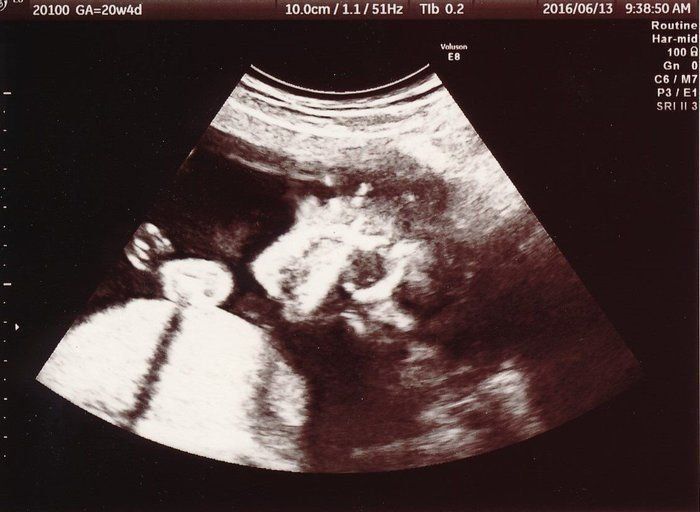

ママにエールさんの妊娠20週目のエコー写真

前回と今回の妊婦検診の間に、実は子宮の硬直と出血を起こして、自宅で安静している期間がありました。その間は、おなかの痛みと、絶え間なく頭に浮かぶ不安に耐える日々…。そのため、このエコー画像で元気な赤ちゃんの姿を確認した時は、体の奥が温かくなったのを記憶しています。顔に手を添える様子がほほ笑ましく、おなかを触りながら何度も見返しました。先生から「無理しない程度に、通常の生活に戻っていいよ」と言われました。